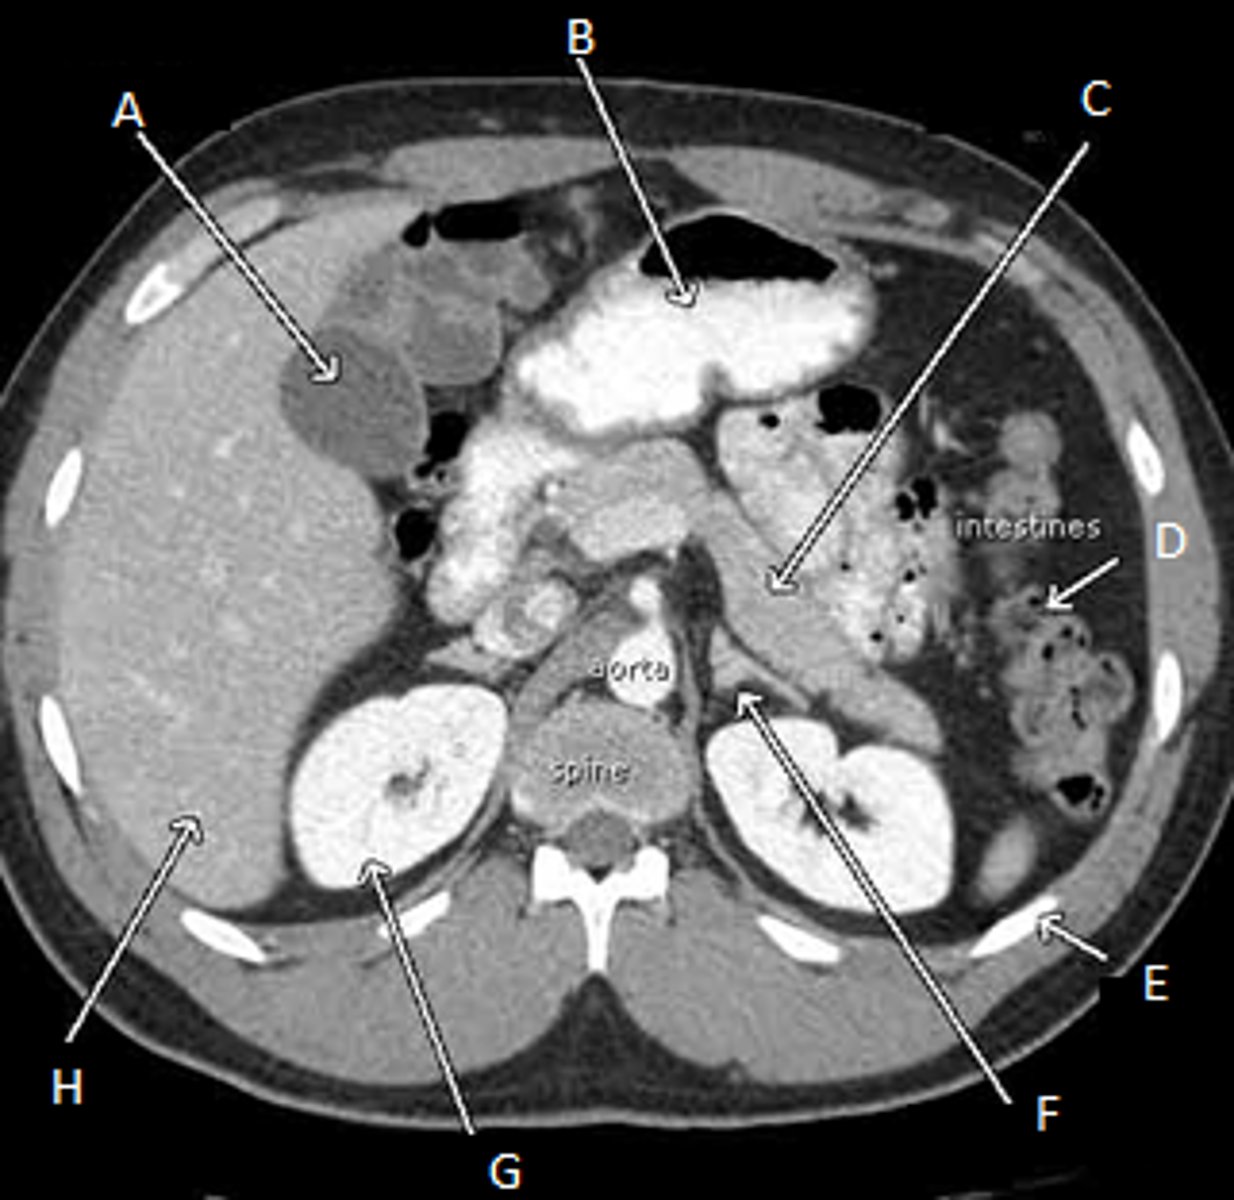

A: Gall bladder

B: Stomach

C: pancreas

D: Intestines

E: Ribs

F: Left Adrenal Glands

G: Right kidney

H: Liver